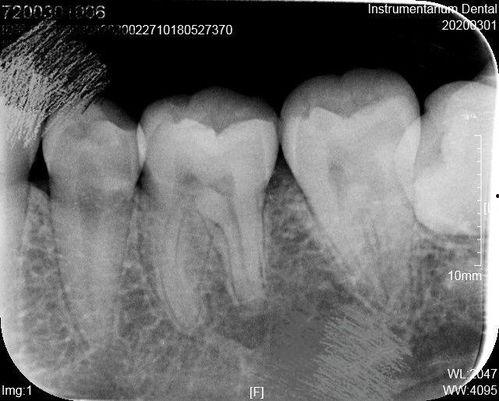

当你意识到自己可能蛀牙了,第一步就是去看牙医。牙医会通过X光片等检查手段,确定蛀牙的程度和位置。如果蛀牙比较严重,就需要拔除蛀牙。